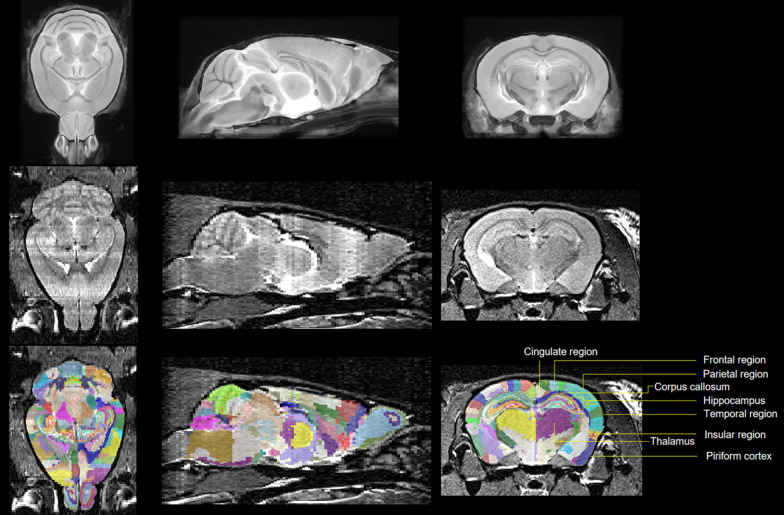

Three-dimensional (3D) brain images were automatically segmented into 364 labels using an in-house pipeline. This consisted of atlas-based brain extraction [29] followed by atlas-based segmentation [30]. In both cases, the atlas used was the high-resolution mouse brain atlas, whose labels include regions such as CA1 which were assigned to super-regions such as the hippocampus [31, 32]. Brain extraction involved linear registration of atlas brain mask to an estimate of the subject’s brain mask (Brain Extraction Tool) [33]. To verify the accuracy of brain extraction, all registrations were manually reviewed. Segmentation required 3D registration of atlas brain to subject brain using both linear and nonlinear registration, with inspection at every stage (Fig. 1). This allowed the transformation of atlas brain regions onto subject brain regions.

Fig. 1.

Each subject was segmented by registration of atlas (top row) to subject (middle row) permitting transformation of atlas brain regions onto subject (bottom row)